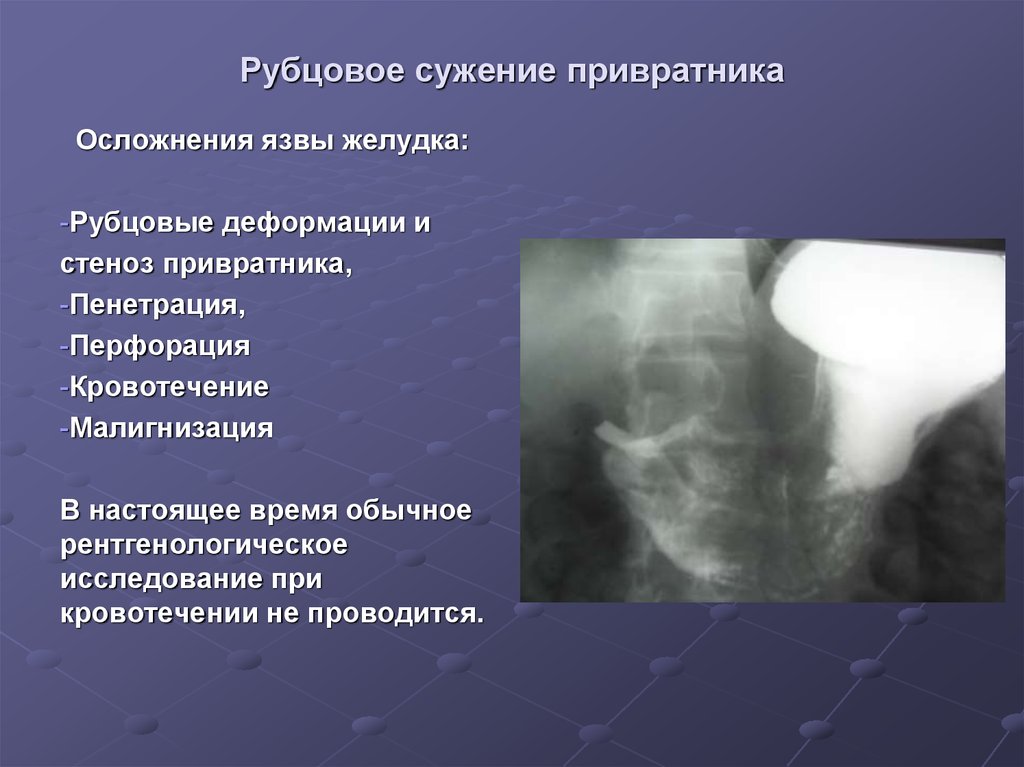

Современные технологии в медицине: рентгенодиагностика заболеваний желудка